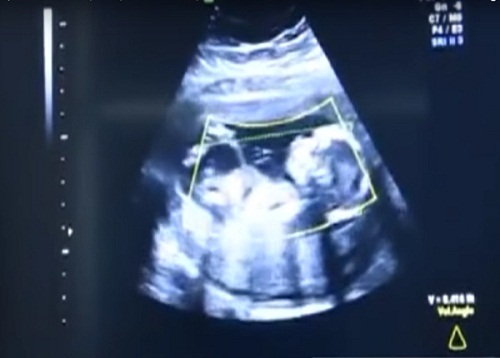

| Bác sĩ phát hiện điều bất ngờ khi siêu âm |

Lúc siêu âm, các bác sĩ kinh ngạc phát hiện em bé không nằm trong tử cung mà lại nằm ở một vị trí trong bụng người mẹ. Cụ thể bà mẹ đang mang thai ngoài tử cung.

Theo đó, thai nhi vẫn nằm trong túi ối bảo vệ như những em bé nằm trong tử cung khác, chỉ có túi ối là không nằm trong dạ con. Các sĩ cho hay, nếu gặp trường hợp này, tỷ lệ em bé sống sót là rất thấp.

| Bác sĩ phát hiện túi ối không nằm trong dạ con |